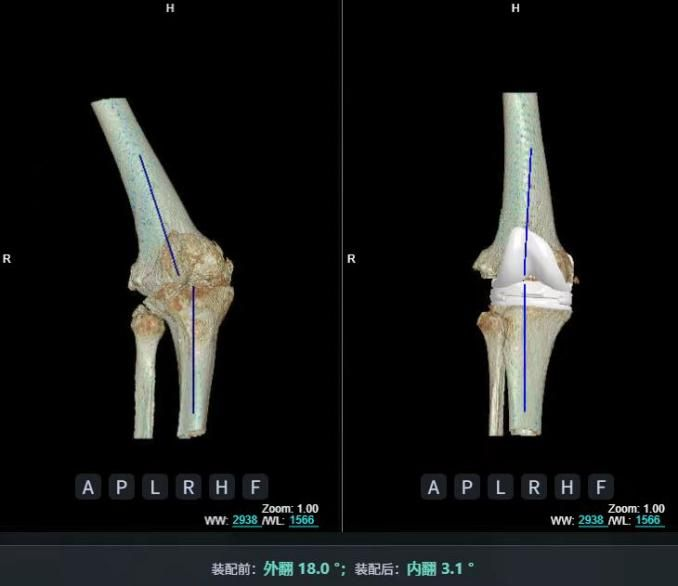

四、精準(zhǔn)微創(chuàng)技術(shù):從關(guān)節(jié)置換到3D打印

4.1 3D打印截骨導(dǎo)板輔助技術(shù)

3D打印截骨導(dǎo)板輔助技術(shù)治療骨關(guān)節(jié)炎,是結(jié)合數(shù)字化醫(yī)學(xué)與3D打印的精準(zhǔn)方案:通過患者CT或MRI影像數(shù)據(jù),設(shè)計(jì)并打印個(gè)性化截骨導(dǎo)板,輔助醫(yī)生術(shù)中精準(zhǔn)定位截骨位置和角度,優(yōu)化手術(shù)效果。

例如,2025年3月,福建醫(yī)大附屬協(xié)和醫(yī)院馮爾宥主任團(tuán)隊(duì)就用該技術(shù)完成一例高難度踝關(guān)節(jié)置換術(shù),為踝關(guān)節(jié)創(chuàng)傷性骨關(guān)節(jié)炎患者治療。[7]

術(shù)中借助3D打印截骨導(dǎo)板精準(zhǔn)截骨、安放假體,僅需小切口即可完成畸形矯正與假體植入;結(jié)合加速康復(fù)理念,患者術(shù)后第3天便能借助助行器下地,康復(fù)科定制的漸進(jìn)式訓(xùn)練計(jì)劃助力其預(yù)計(jì)1個(gè)月內(nèi)獨(dú)立行走,術(shù)后X線顯示假體位置理想、關(guān)節(jié)力線完美恢復(fù)。

比較傳統(tǒng)踝關(guān)節(jié)置換術(shù)依賴術(shù)中反復(fù)透視調(diào)整截骨角度,存在操作復(fù)雜、輻射暴露多、假體匹配等不足,3D打印假體踝關(guān)節(jié)置換術(shù)可將手術(shù)誤差控制在毫米級,術(shù)中透視次數(shù)減少50%以上,手術(shù)時(shí)間縮短至1-2小時(shí),患者術(shù)后次日即可開始康復(fù)訓(xùn)練。